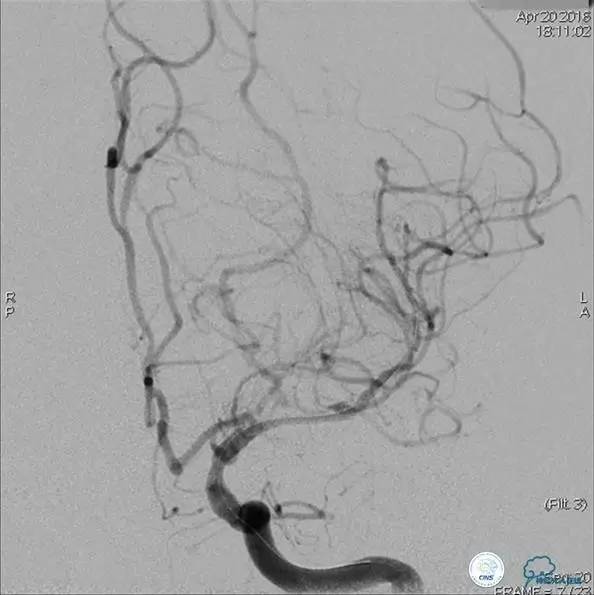

患者:49岁男性,左侧偏瘫1个月,药物治疗、康复训练效果不好,转我院,肌力0~1级。

core-clilnical明显不匹配,是介入开通的合适患者。

造影评价血管、判断闭塞段,微导丝小心穿过闭塞段,微导管造影,交换技术,球囊扩张,Enterprise支架。在后扩张时导丝刺破M3段血管,蛛网膜下腔出血(SAH)。

微导管进入破裂血管,栓塞弹簧圈1枚,出血停止,结束手术。继续双抗,术后2天肌力2级,神经功能恢复明显加快。

术后即刻和6天后CT,患者无明显临床症状。

半年后复查造影,无支架内再狭窄,可见弹簧圈,患者恢复至自己柱杖行走。